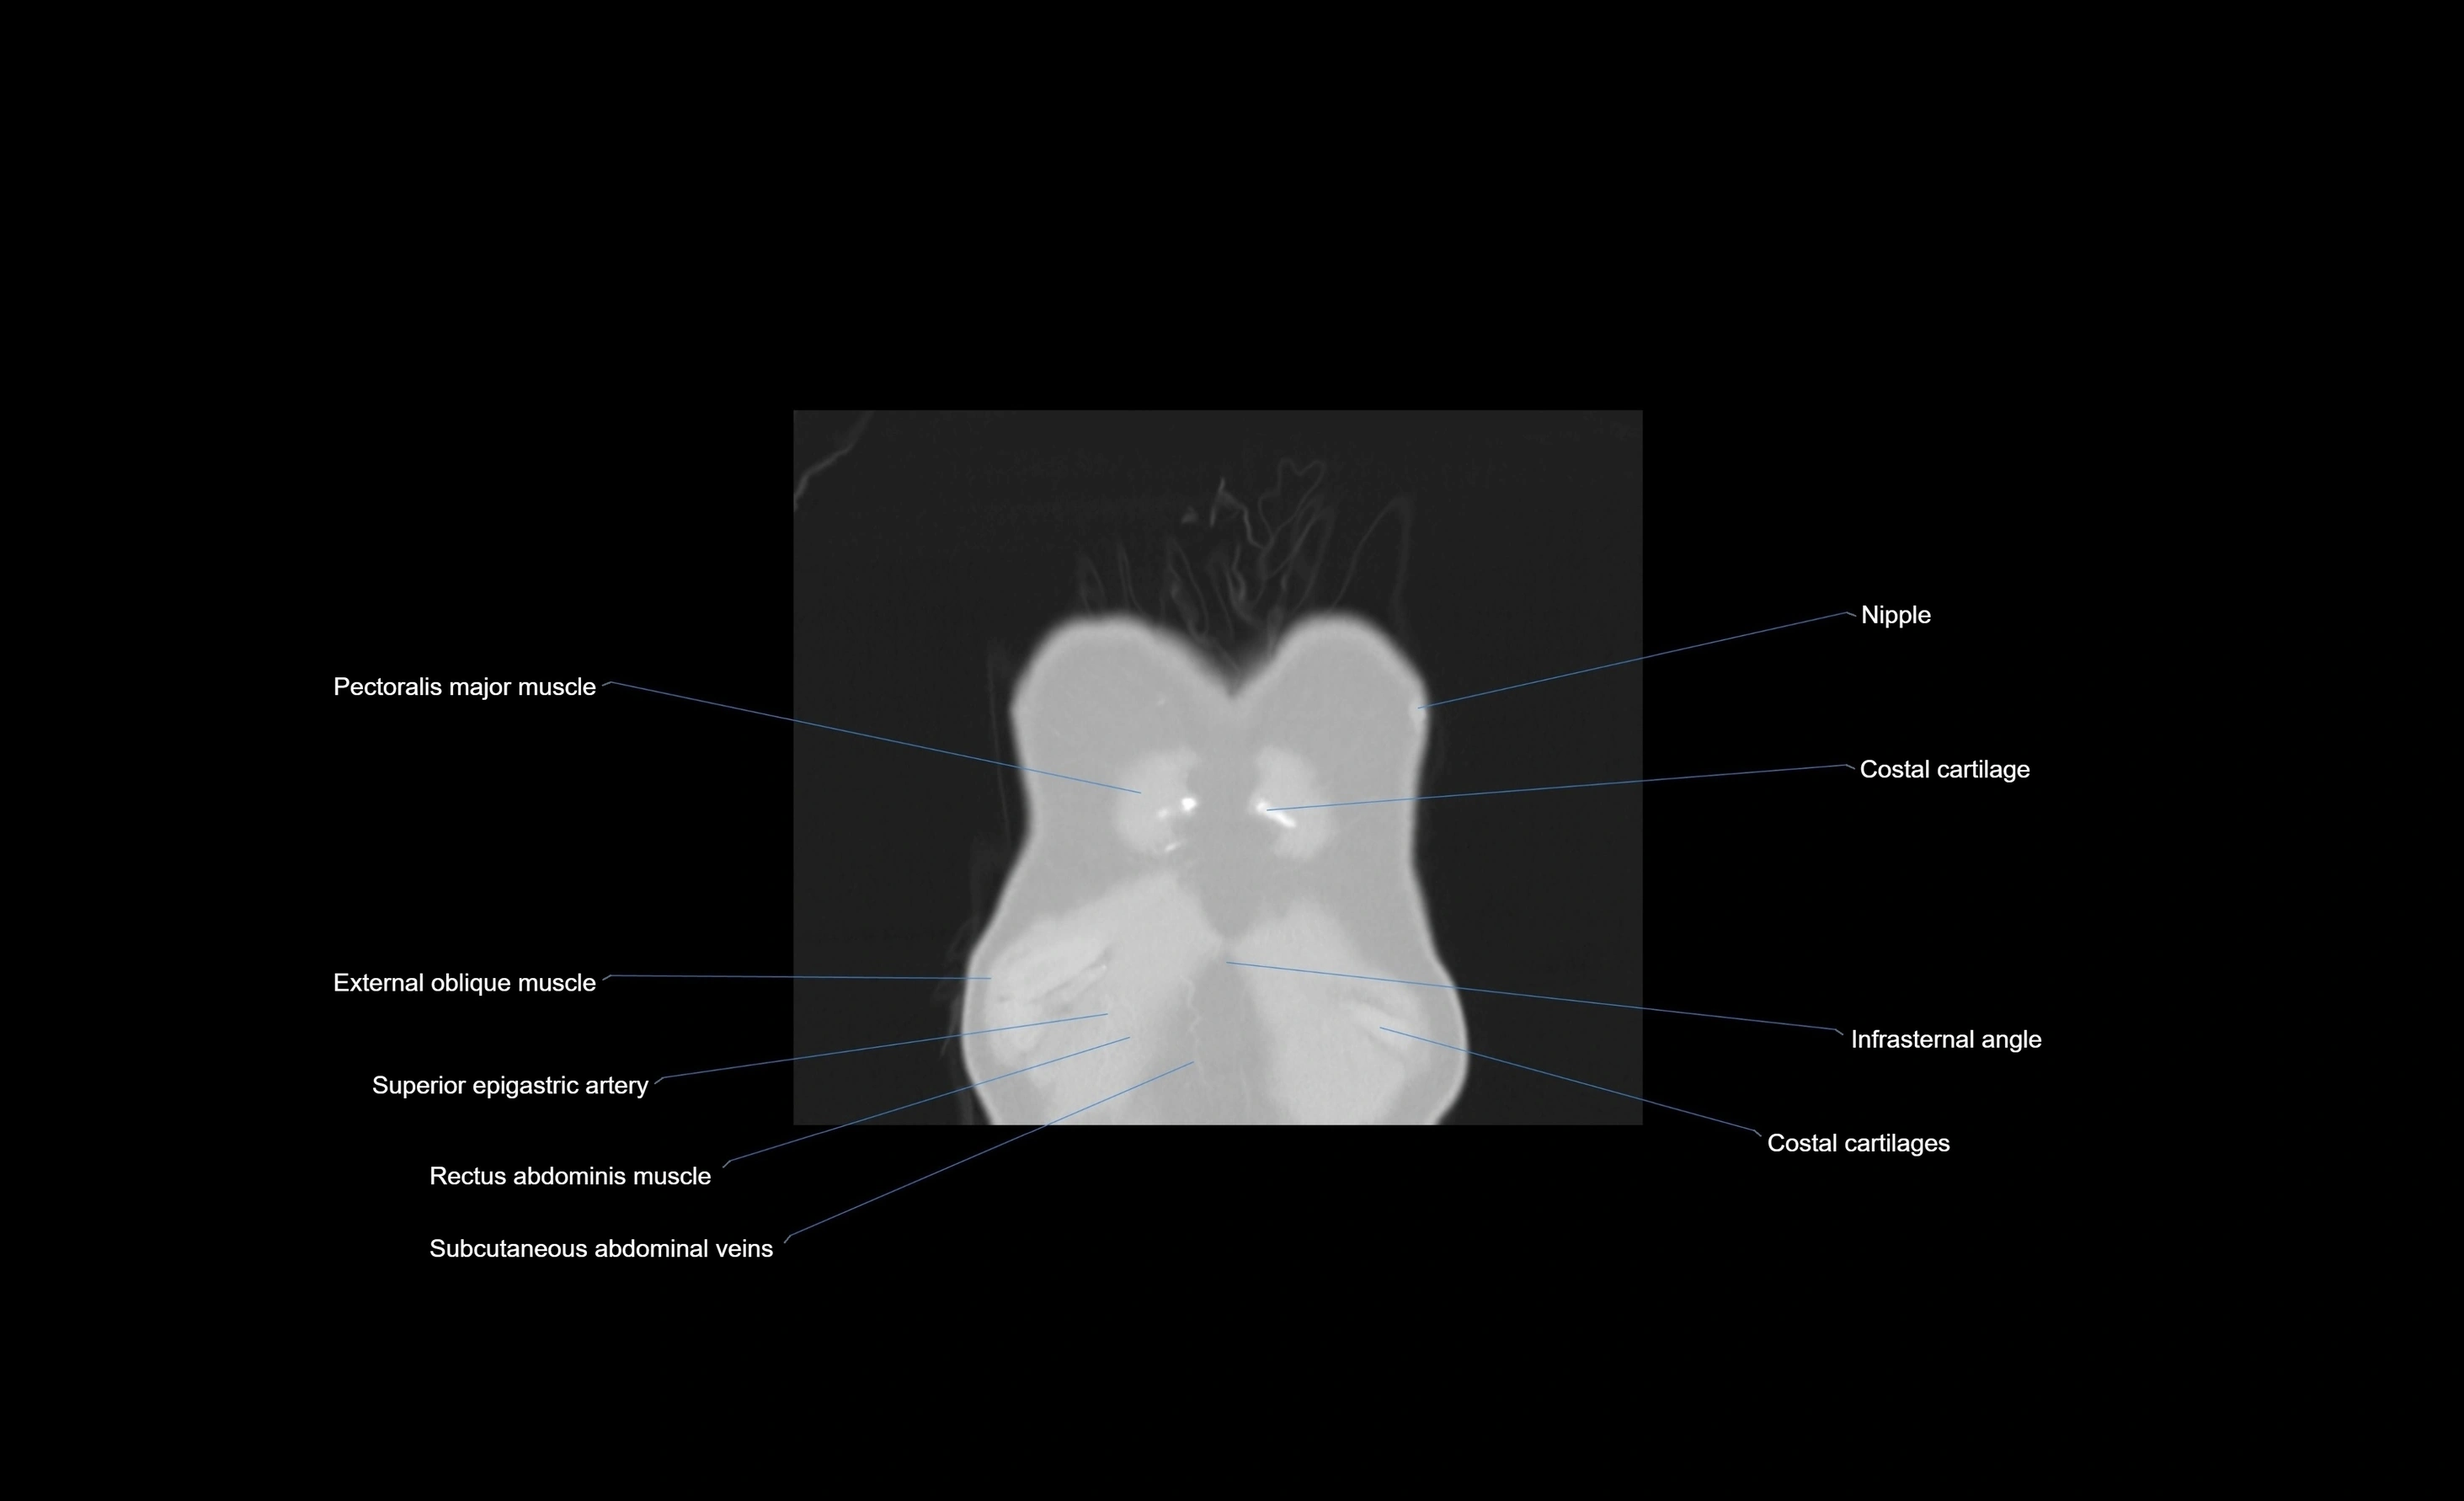

CT images